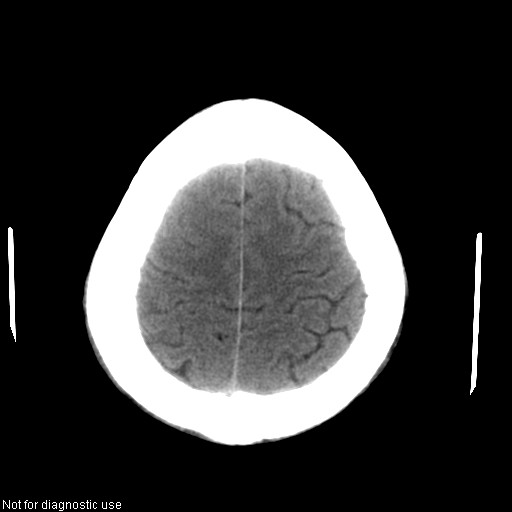

以下是引用hhcckk在2008-1-26 16:03:00的发言:[br]考虑病毒感染可能性大[br]1、病人发病时间短,1周,转移病灶时间长[br]2、楼主虽然没有告诉我们年龄,但从颅内情况来看,病人年纪不会很大,脑池,脑沟不是很明显,当然,可能有脑肿胀的原因,转移灶病人年纪一般较大[br]3、从病灶特点来看,转移多发生在灰白质交界区,多有指状水肿,占位效应明显,此病人呈对称性发布,发生在脑实质深部,与转移有所区别[br]4、病人经抗炎,止咳效果不好,可能是病毒感染,抗生素治疗效果不好[br]5、建议楼主1、增强 2、有呼吸系统的症状何不拍个胸片